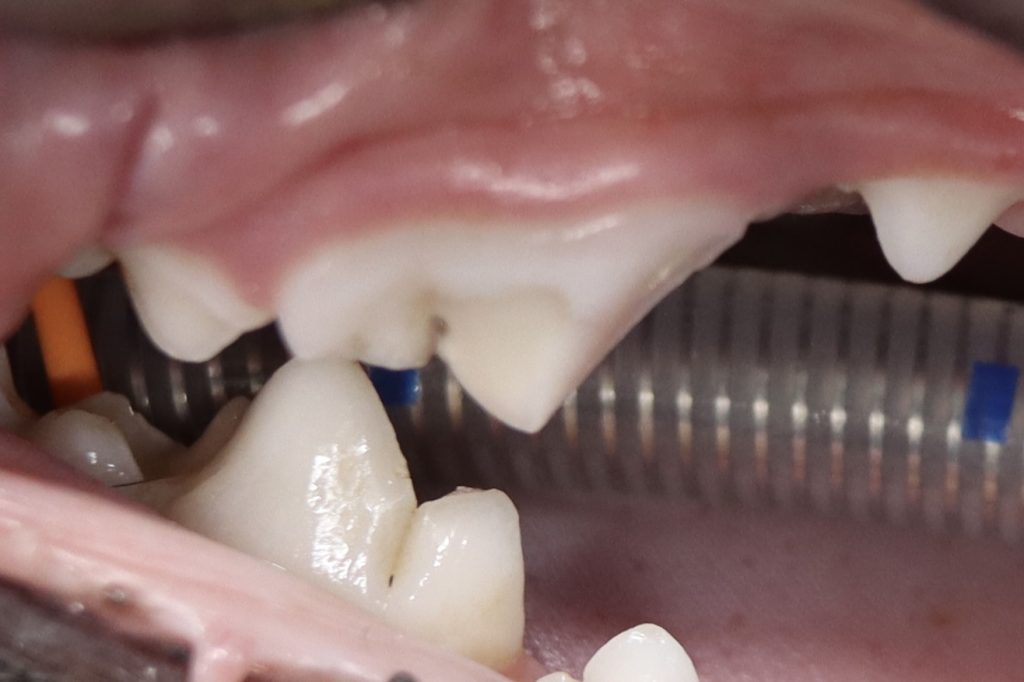

今回のブログは犬で多い第四前臼歯の破折歯の治療の解説です。

・ラバーダムの設置

この第四前臼歯は三根歯のためそれぞれの歯髄に対して治療を行う必要があります。